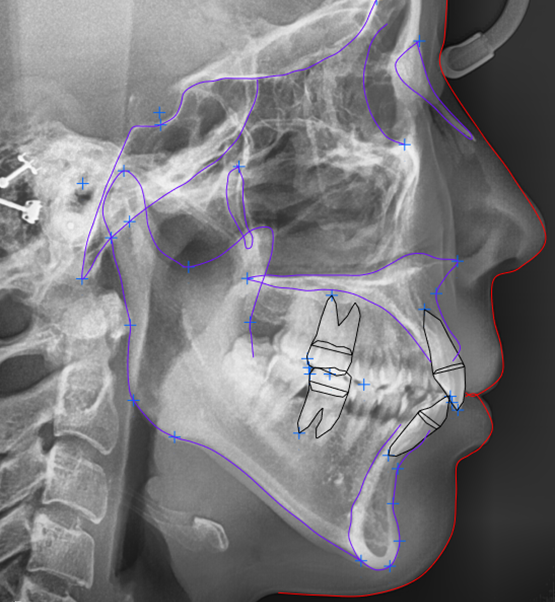

촬영일 :23.06.09

전치부 치근을 확인해 본 결과,

다행히 치아 뿌리의 길이가

교정을 하게 된다 하더라도

양호한 것으로 판단됩니다.